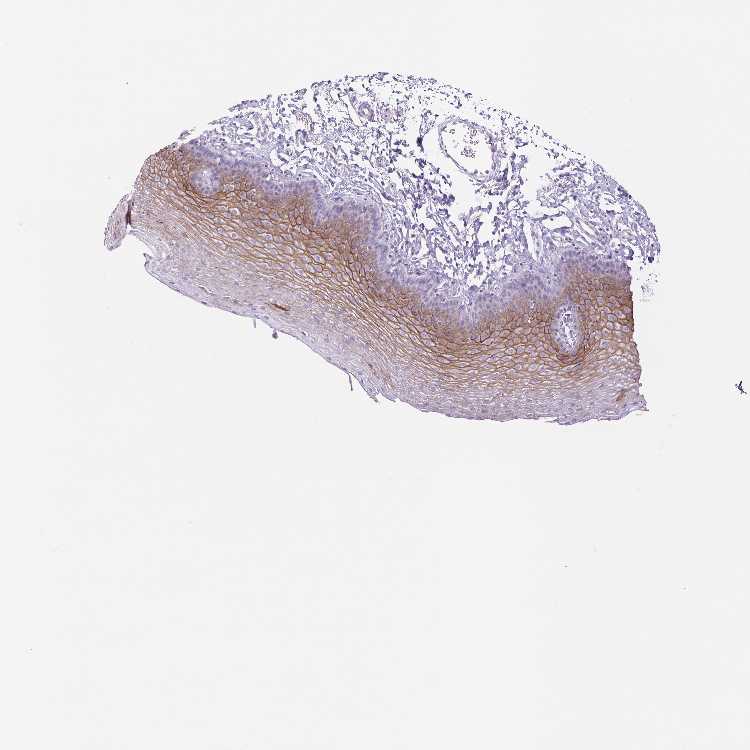

ESOPHAGUS - Antibody stainingi

Antibody staining in the annotated cell types in the current human tissue is reported as not detected, low, medium, or high, based on conventional immunohistochemistry profiling in selected tissues. This score is based on the combination of the staining intensity and fraction of stained cells.

Each image is clickable and will lead to virtual microscopy that enables deeper exploration of all samples and also displays staining intensity scores, fraction scores and subcellular localization as well as patient and tissue information for each sample.

Antibody HPA044730Antibody HPA054184

Squamous epithelial cells Not detectedMedium